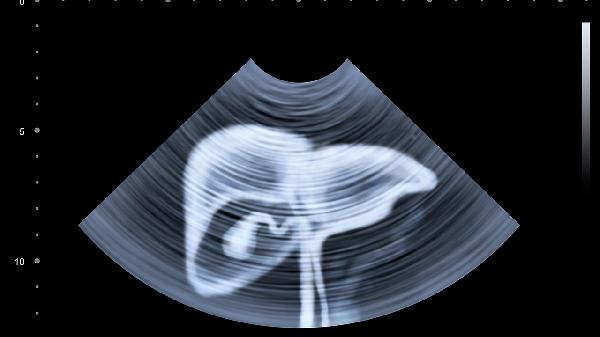

肝脏钙化点可能与肝内胆管结石、寄生虫感染、肝血管瘤、肝结核、肝脏陈旧性损伤等因素有关,通常表现为右上腹隐痛、乏力、食欲减退等症状。可通过超声检查、CT扫描等方式确诊,并根据病因采取药物或手术治疗。